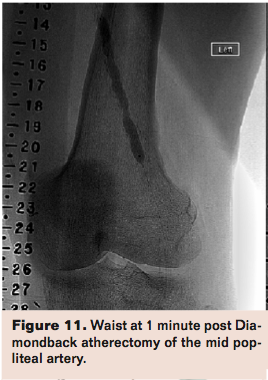

Compliance 360 was the same design but in 50 patients with FP lesions. Adjunctive stenting was needed in 8% in the OA arm vs 84% in the PTA arm (P<.0001). Mean maximum balloon pressure (a measure of lesion compliance) in the OA arm was 3.9 atm vs 9.1 atm in the PTA arm (P<.0001). Freedom from TLR (including acute adjunctive stenting) or restenosis at 6 months was met in 72.7% of the OA arm and 8.3% of the PTA arm (P<.0001). By 12 months, restenosis or repeat TLR occurred in 5 of 21 in the PTA arm (4 in-stent) and 5 of 20 in the OA arm (P=NS).18 The CONFIRM registry series was designed to evaluate OA in PAD of lower extremities, as well as to optimize the OA technique. It studied a total of 3,135 patients originally enrolled in either CONFIRM I (Diamondback 360); CONFIRM II (Predator 360); and CONFIRM III (Diamondback 360, Predator 360, and Stealth 360). Eighty-one percent of lesions had moderate to severe calcification with an average preprocedural stenosis of 88% as adjudicated by the treating physician. Treatment with OA reduced stenosis from 88% to 35%. Final residual stenosis after adjunctive treatment (low-pressure PTA at a mean of 5.5 to 5.8 atm) averaged 10%. The key take-home points from the series were that shorter spin times and the use of smaller crown sizes significantly decreased procedural complications including slow flow, vessel closure, and spasm.19 This illustrates the concept that plaque modification provides better outcomes than plaque debulking. As evidenced in the studies, OA is effective in the treatment of calcified lesions in the FP segment as well as below the knee. As a limitation, these studies share the lack of core lab adjudication of angiographic data. In summary, compared to PTA alone, OA with low pressure PTA leads to better luminal gain by improving lesion compliance with less need for adjunctive stenting when treating calcified FP lesions. Patency at 12 months is comparable to PTA with a provisional stent strategy. Occasionally, a lesion continues to show a “waist” (Figure 11) after Diamondback atherectomy. This should be treated with repeated Diamondback atherectomy followed with repeated low-pressure balloon angioplasty (Figure 12).